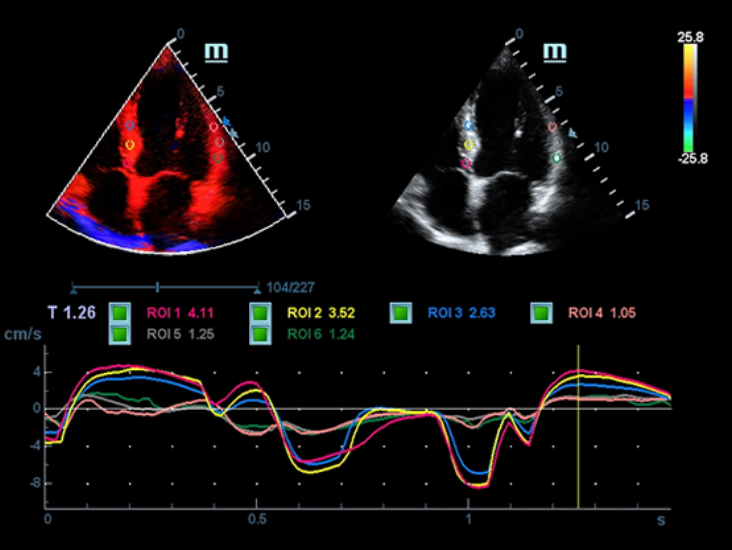

Sobre la base de un profundo conocimiento de las necesidades del cliente, el DC-60?ECHO con X-Insight estå dise?ado para brindar alta eficiencia con imågenes precisas, lo que se ve potenciado con eXpress Clarity (claridad exprés), eXceptional Intelligence (inteligencia excepcional) y eXceeding Experience (experiencia extraordinaria).

eXceeding Experience

Experiencia con alta productividad